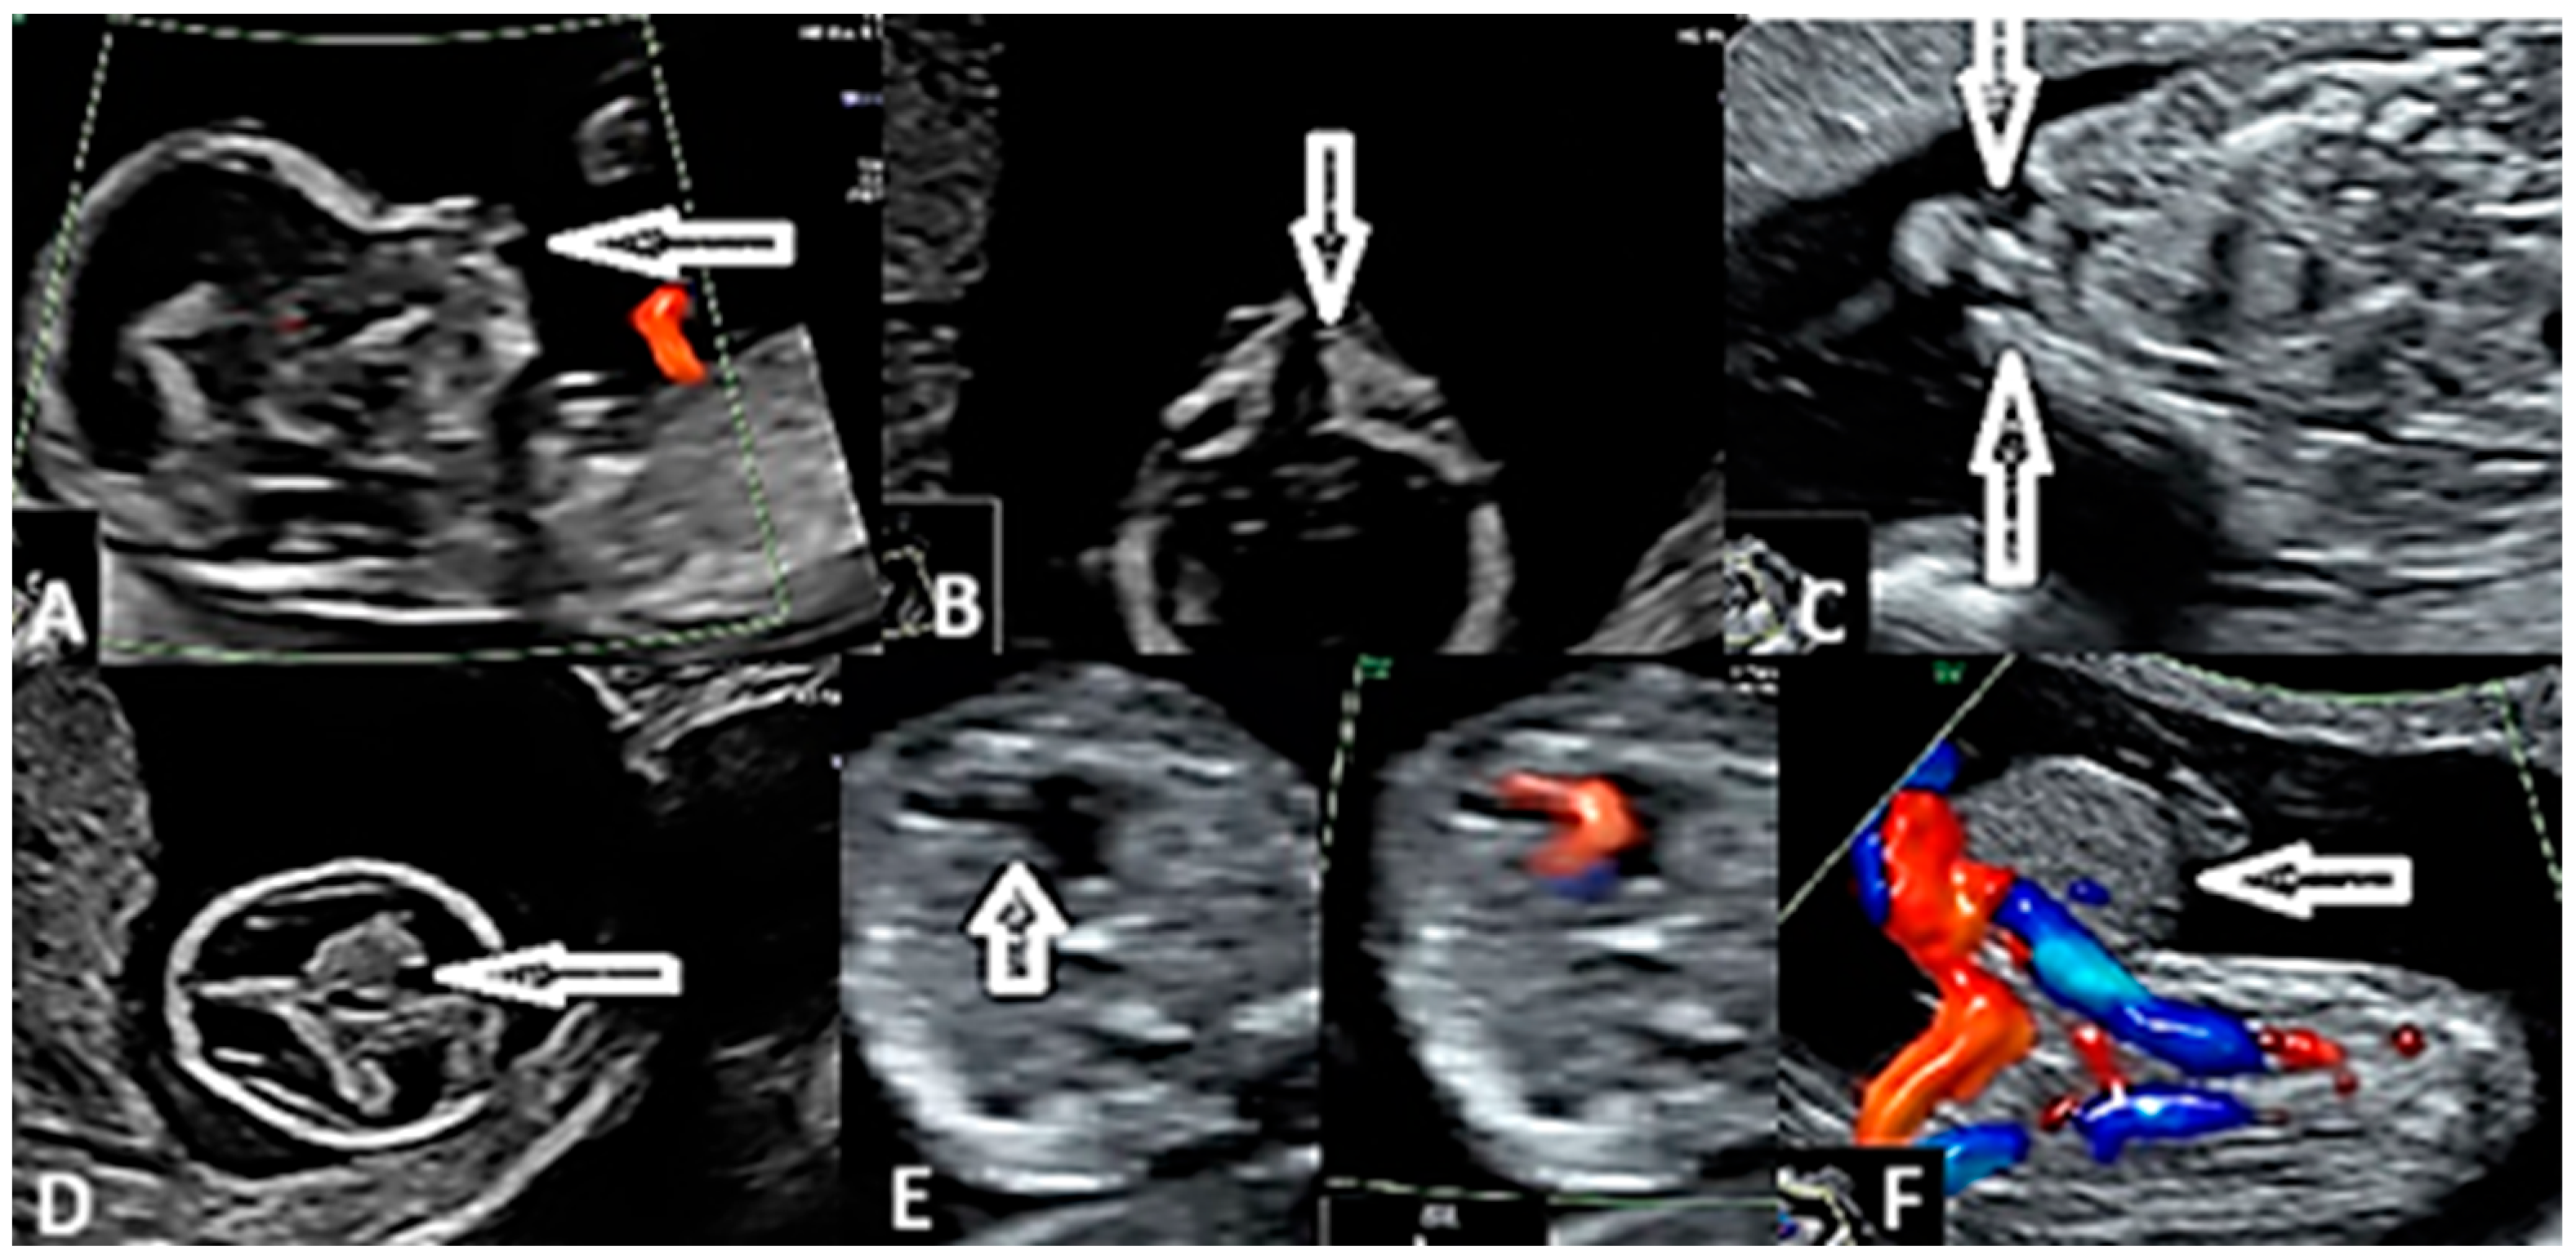

| Heart | 16 | 16/58 (27.5%) | |

| Double outlet right ventricle | 2 | 2/58 (3.4%) | <0.01 |

| D-transposition of the great arteries | 2 | 2/58 (3.4%) | <0.01 |

| Univentricular heart | 4 | 4/58 (6.8%) | <0.01 |

| Complex cardiac malformation | 5 | 5/58 (8.62%) | <0.01 |

| Tricuspid valve atresia with VSD | 1 | 1/58 (1.7%) | <0.01 |

| Major interventricular septal defect (VSD) | 1 | 1/58 (1.7%) | <0.01 |

| Tetralogy of Fallot | 1 | 1/58 (1.7%) | <0.01 |